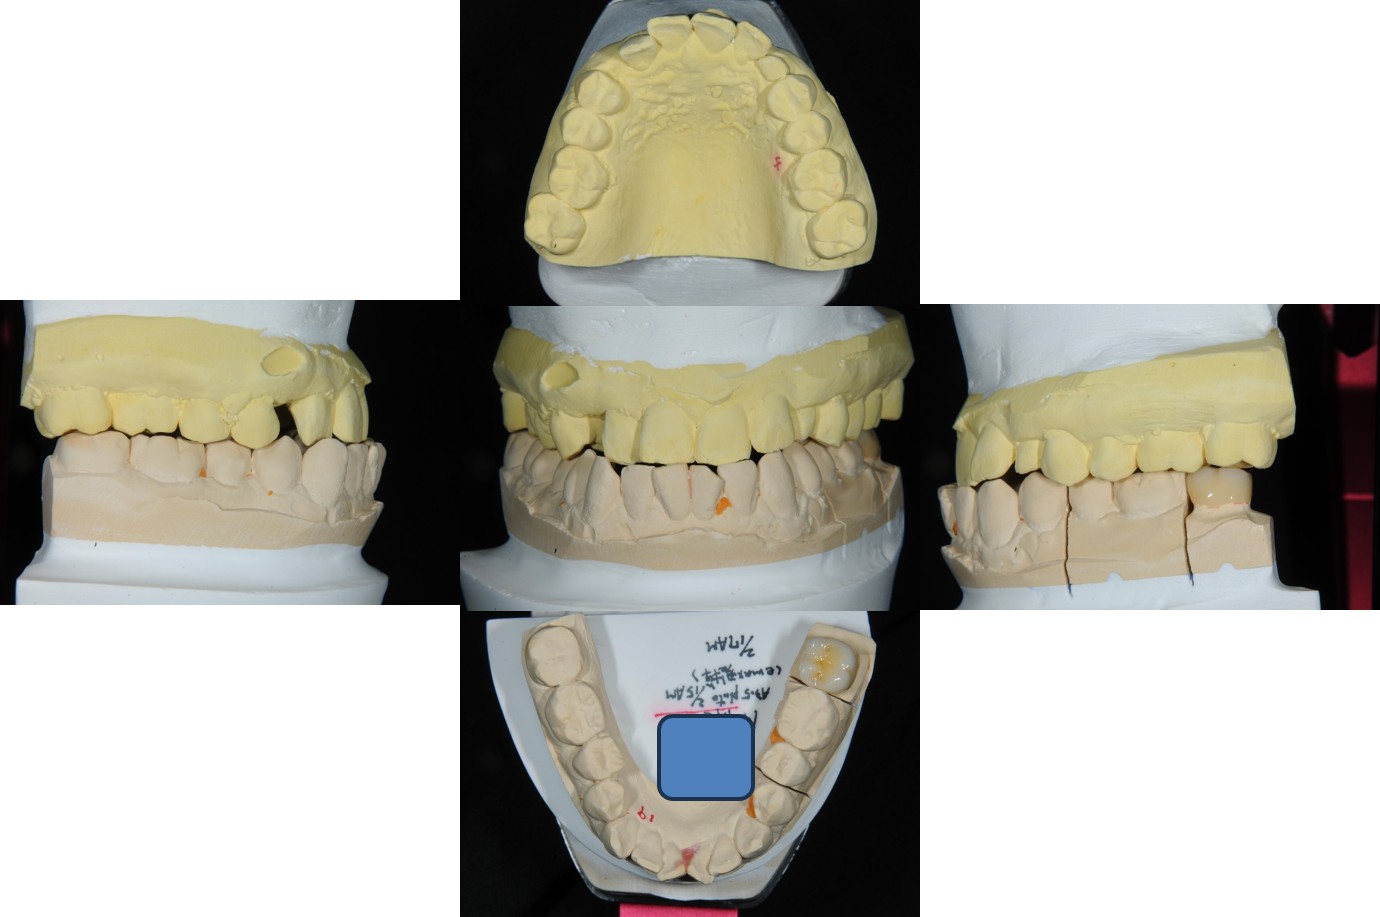

上面弓、上咬合器

技師於咬合器製作全瓷冠

術前、術後比較